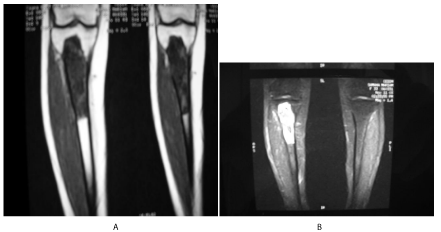

A 33 year - old female patient presented for right leg pain of a five week duration, exacerbated by weight bearing without disappearing at rest or at night. She estimates the pain as 6 over 10, relieved with non-steroidal anti - inflammatory agents. She is previously healthy without any history of trauma. There is mild edema, no redness, and mild increase of the pain upon palpation. There are no neurovascular abnormalities. Examination of the back, hip, and knee is normal. X-ray showed a large hypolucent spherical lesion in the proximal third of the tibia (Figure 1). MRI on T1 showed the lesion to be hypointense, and on T2 to be hyperintense (Figure 2,3). The lesion showed to be osteolytic, extending anteroposteriorly through the cortex at some levels, but it did not reach the articular surface, nor the surrounding soft tissues. Decision was taken to biopsy it. The pathology report showed lamellated cysts and scattered scoleces. Albendazole 400 mg was given orally twice per day for 2 months. Extensive curettage was done through excision of bone layers with a burr, then phenolization and grafting of cancellous bone chips inside the cavity. The patient was free clinically and radiologically of the disease for two years, then in the third year, multilocular cysts reappeared on x-ray (Figure 4), with possible extension to the articular surface. A decision of total knee arthroplasty was taken after wide resection of the diseased segment (Figure 5). Negative margins were obtained. The patient post operatively was rehabilitated; pain subsided with no radiological signs of recurrence. She was given albendazole 400 mg orally twice per day for 3 months.

Figure 2: On the left: T1 coronal cuts showing hypointense proximal tibia lesion not reaching the articular surface, nor invading the surrounding soft tissues. On the right: T2 coronal cuts showing hyperintense lesion.

Figure 3: Transverse T1 cuts, showing the anteroposterior involvement of the tibia. No soft tissue invasion.